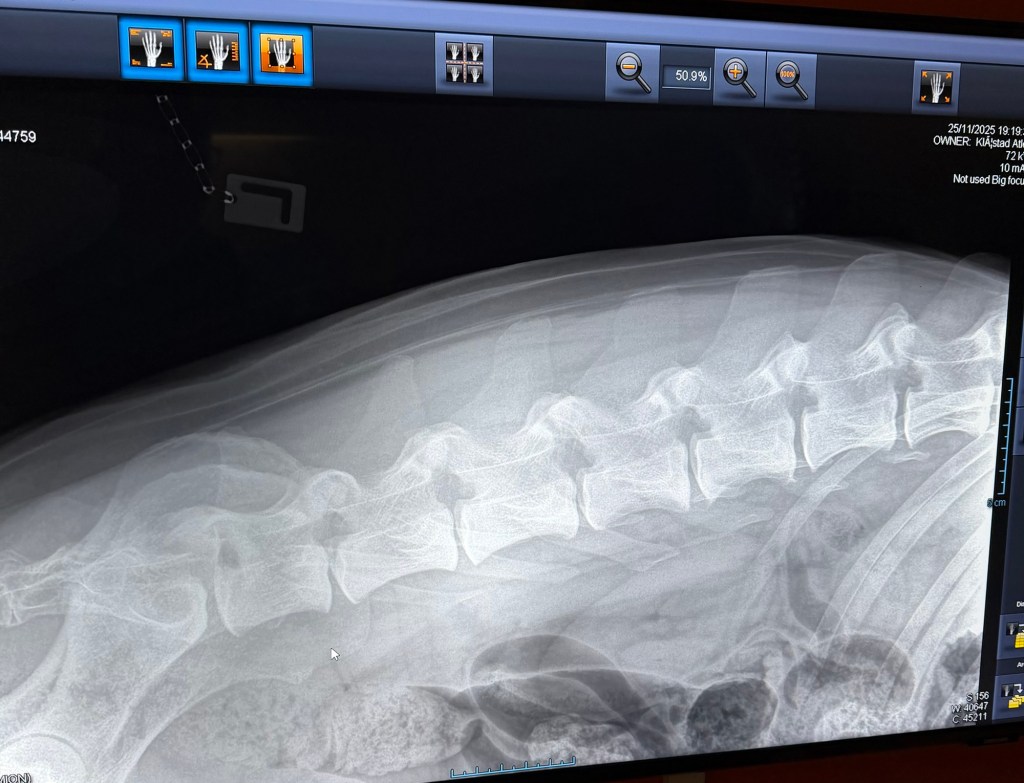

Freki har også vært på røntgen nå i november 2025, i en alder av 3år og 8måneder. Dette grunnet et ønske om å avdekke eventuelle svakheter eller forandringer i skjelett. Freki er en kraftig og stor hund med mye muskler og kraft, så her er det store påkjenninger. Rygg og albuer ble sjekket og resultatene var fantastiske og meget bra! Han har mikroskopiske forandringer i rygg og en flott bakpart med robust lende-rygg. Albuene er som tidligere, uten stor signifikant forandring. En frisk og sunn 4 åring! Freki har et utrolig flott vesen og er en ordentlig glad Bamse-gutt med masse kjærlighet til alle.